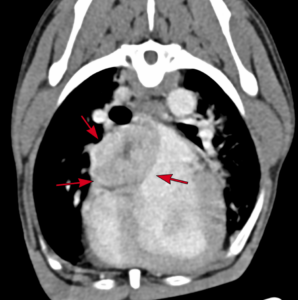

Barney, a 9 year old Soft-Coated Wheaten Terrier, presented to Northern Ireland Veterinary Specialists (NIVS) due to a 3 month history of refractory ascites and documentation of a cardiac mass by his primary vets, Banbridge Pet Vets. Investigations at NIVS by Julie Hamilton Elliott (RCVS and EBVS® Specialist in Veterinary Cardiology) confirmed the cardiac mass was causing compression of caudal vena cava entering the right atrium. This was resulting in Budd-Chiari syndrome with subsequent hepatic venous congestion and ascites. Computed Tomography (CT), performed for surgical planning, confirmed a large 4×3.7cm mass located between the right and left atrium with no evidence of secondary metastatic disease.

The minimally invasive, fluoroscopic-guided procedure involved accessing both the right jugular and left femoral veins. The location and extent of the mass was first determined by a contrast angiographic study. A series of catheters and guidewires were then used to deploy a woven Nitinol stent extending from the caudal to the cranial vena cava, through the right atrium. Repeat angiography revealed improved caudal vena caval flow and Barney recovered uneventfully. He was discharged the following morning.